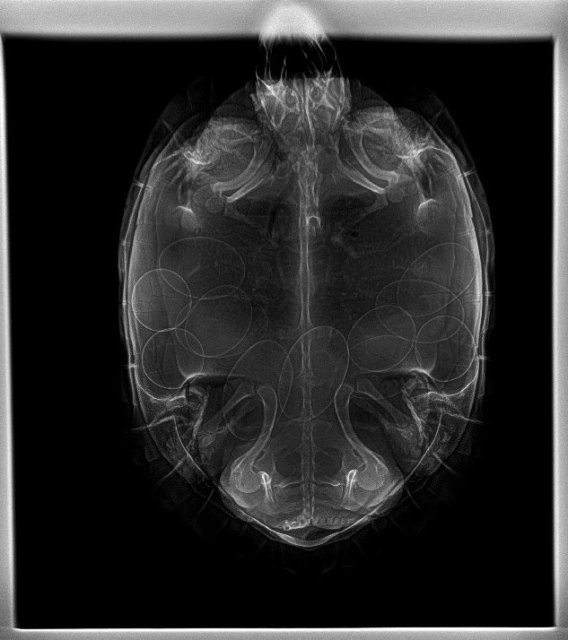

@moth Здравствуйте ! Возил Тору к Савиной, сделали рентген.

___0003.thumb.jpg.33d3a08412a47f21e5d9a9c322dcd7fe.jpg  ___0002.thumb.jpg.a5f75ef987d5f7724d01bca4350c13e1.jpg

Яиц много, сказала пока следить, если через 15 дней не будет готовиться к кладке - сделать укол кальция. Так все нормально ?

@Алексей Alex-Raduga ух сколько

я бы уже начала кальций колоть, не надо ждать ещё 2 недели

@Алексей Alex-Raduga хорошо, что получилось снестись. Это прям много яиц, тяжело ей было, конечно